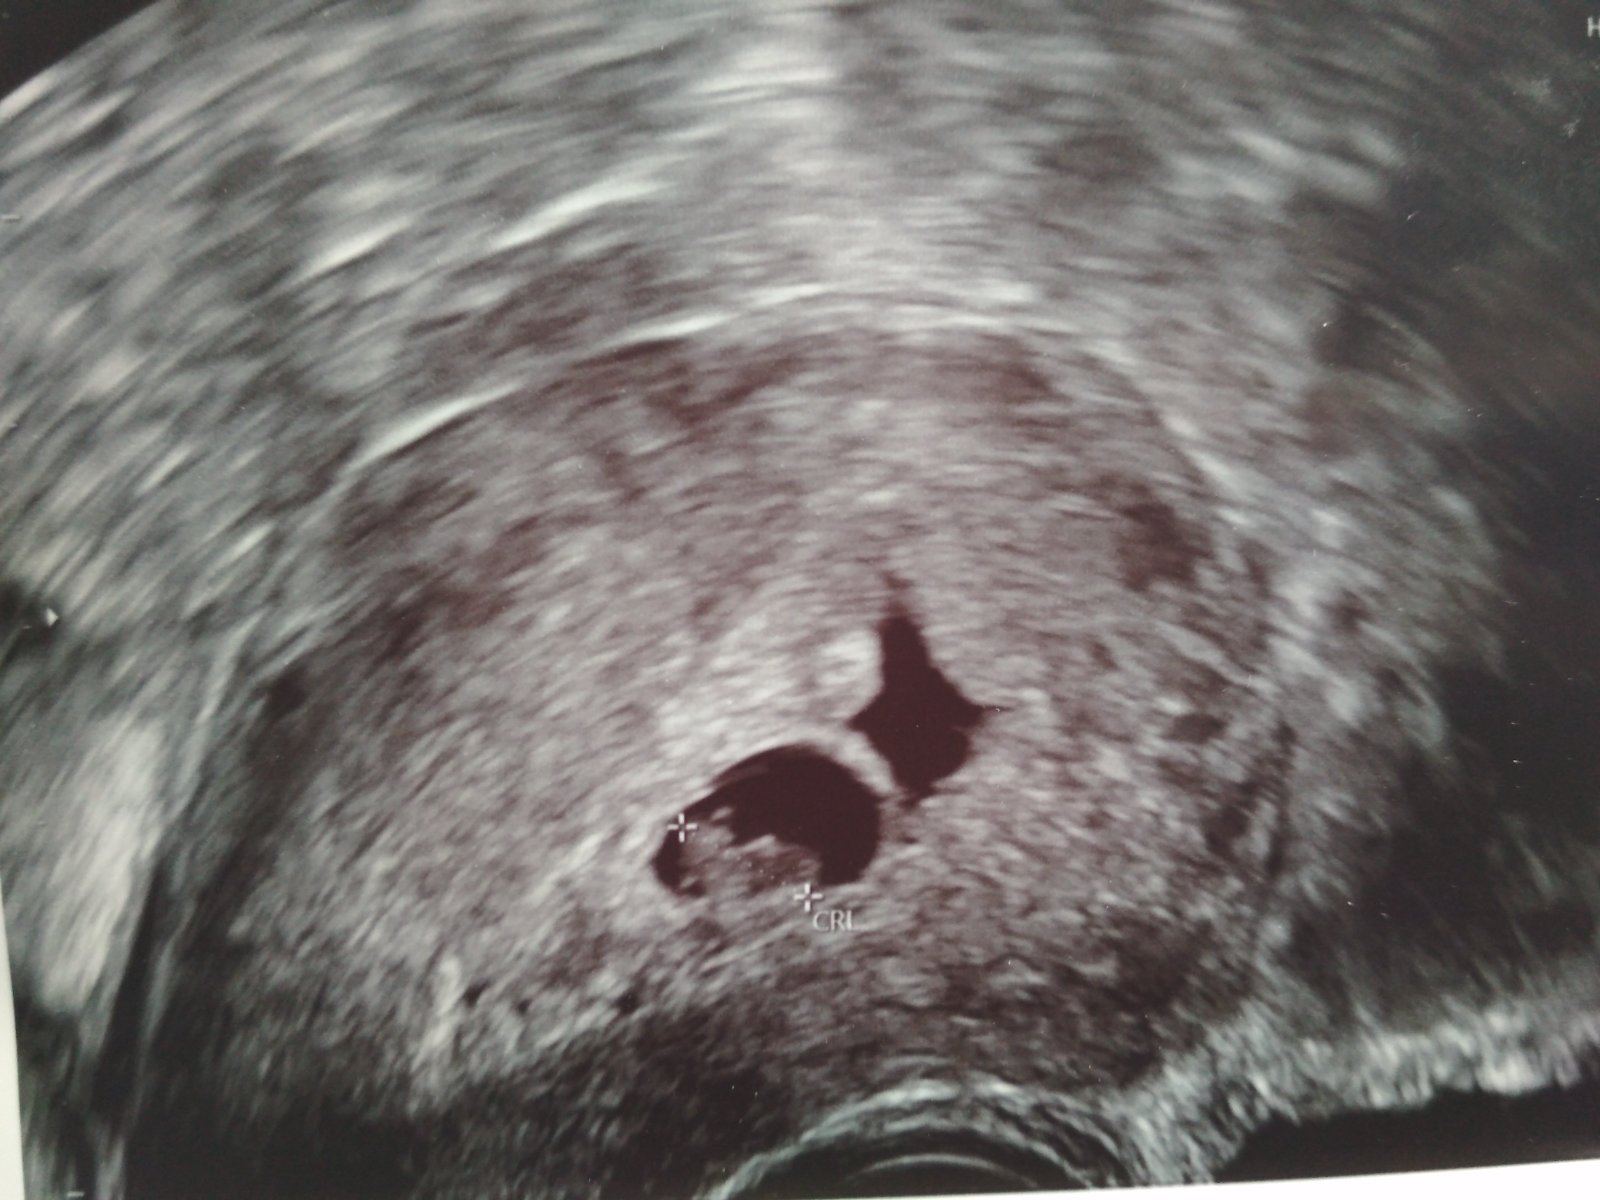

Dnes jsem byla na kontrole u dr,, těhotenství dle ovulace 7+0, podle ult 6+5 ❤️. "Miminko" má skoro 8 mm a srdíčko bije o stošest, tam žádný problém neshledán❤️. Jenže je tam jiný problém, co zarazilo paní doktorku... Nad plodovým vejcem je částečné odloučení 😞. Dr říkala, že to odloučení pravděpodobně bude naplněné krví a je velká pravděpodobnost, že začnu špinit nebo krvácet... Dala mi léky na krvácení a jak se objeví nějaký náznak, mám to hned začít zobat, a pokud to krvácení bude větší, tak hned na kontrolu ke své dr. nebo do nemocnice ...

Přikládám fotku, kde je to odloučení vidět... Jaké prosím bývají prognózy u této komplikace?